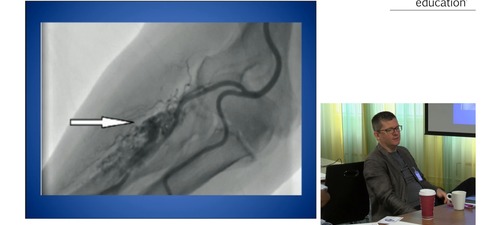

Neil Ruparelia outlines complications of PCI, with case examples